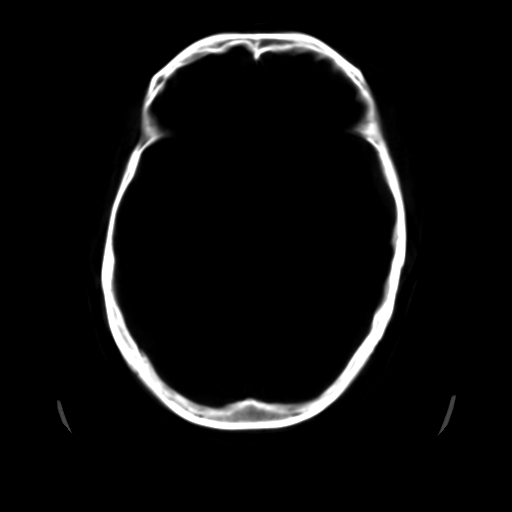

标题: CT25225:男,51岁,头外伤一小时。 [打印本页]

标题: CT25225:男,51岁,头外伤一小时。

男,51岁,头外伤一小时,呕吐两次。

蛛网膜下腔出血 脑肿胀

1)左侧中颅窝蝶骨翼后方硬膜外血肿。2)左侧颞顶部硬膜下血肿。3)蛛网膜下腔出血。4)左侧筛窦及双侧蝶窦炎症(或积血)。5)左侧额部头皮软组织肿胀。

1:左侧硬膜外及硬膜下混合血肿。2:蛛网膜下腔出血。3:左额部少量颅内积气?